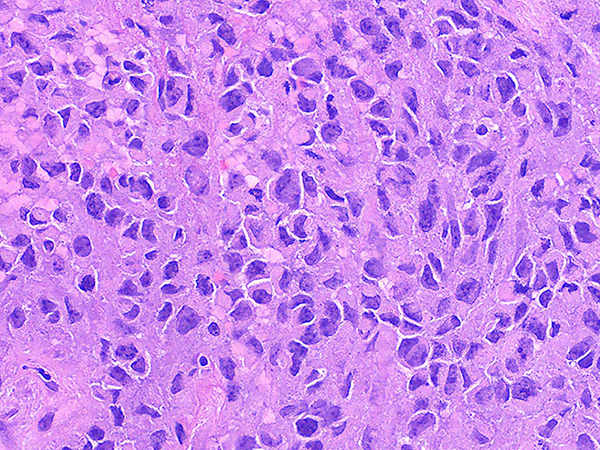

Clinical History: Middle aged man with a large central lung tumor. Endobronchial biopsies demonstrate a poorly differentiated high grade neoplasm with abundant necrosis (Figures 1-2). The tumor is composed of round to oval discohesive cells with prominent nucleoli, abundant mitotic activity and a relatively monomorphic appearance (Figures 3-5). Numerous rhabdoid cells with distinctive eosinophilic cytoplasmic inclusions indenting eccentrically located nuclei are present (Figures 3-5). The neoplastic cells are negative for all cytokeratins including, 7, 5/6, AE1/AE3, OSCAR and cam 5.2. The cells are negative for neuroendocrine markers synaptophysin, chromogranin, and CD56. The cells are also negative for CD45, TTF-1, p40, NUT, SOX10, CD31 and desmin. The cells have intact expression of INI-1. The neoplastic cells demonstrate complete loss of BRG1 expression (Figure 6).

These tumors have a characteristic appearance with discohesive high-grade round cells and focal rhabdoid cells with eosinophilic inclusions that indent the eccentrically located nuclei (Figures 3-5). These tumors typically have a more monomorphic appearance but have prominent nucleoli, abundant mitotic activity and necrosis. Expression of the cell adhesion molecule Claudin-4 and the SMARCA2 protein (another major catalytic subunit of SWI/SNF complexes) is also typically lost in these tumors.